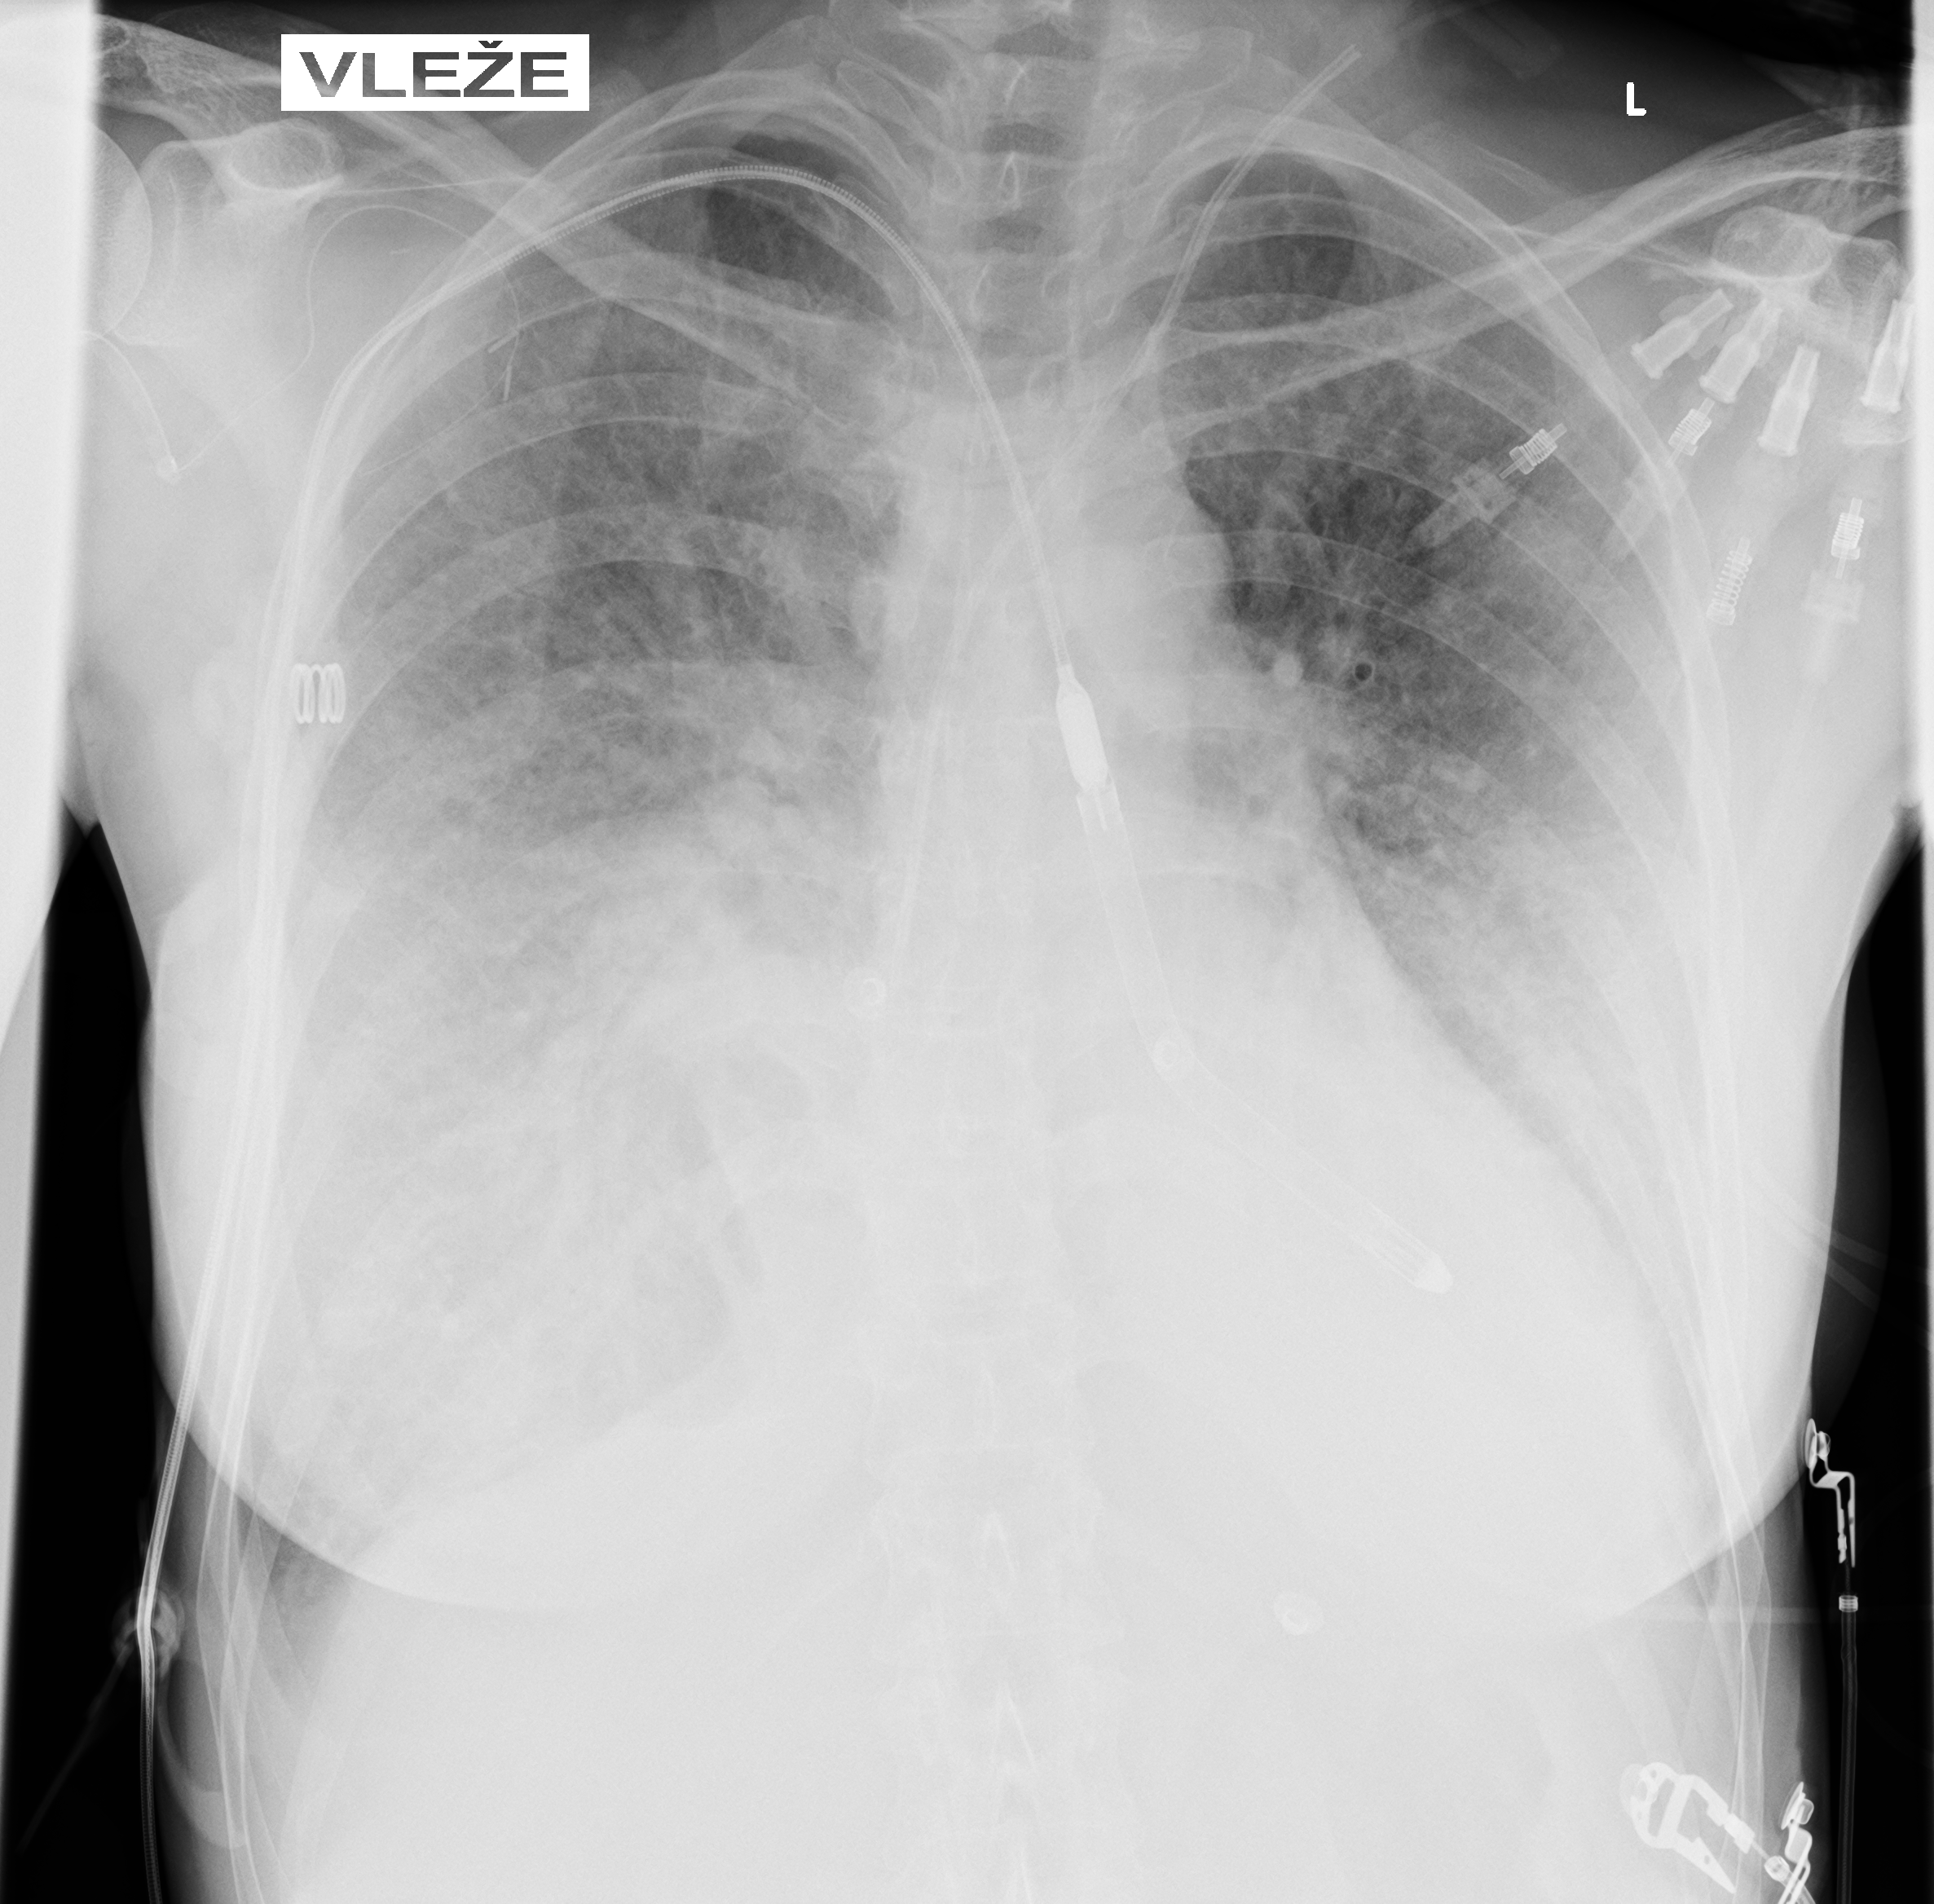

Due to persistent severe LV dysfunction and risk of cardiogenic shock, Impella 5.5 was implanted on day 3 for LVunloading.

Correct position was assessed by TEE and CXR

During hospitalization, the patient’s clinical condition gradually improved. By day 24, she tolerated P-1 support at 0.8 L/min, allowing successful discontinuation of mechanical circulatory support. She was subsequently transferred to a standard ward and, after several days, discharged home on ongoing immunosuppressive therapy with tacrolimus and mycophenolate mofetil, together with tapering corticosteroids. Long-term, likely lifelong, immunosuppressive therapy is anticipated.

The use of the Impella 5.5 device enabled early initiation and rapid up-titration of guideline-directed heart failure therapy, which was subsequently continued and optimized in the heart failure outpatient clinic.

Echocardiography Before Discharge

• Left ventricular ejection fraction improved to 50–55%

• Borderline right ventricular systolic function